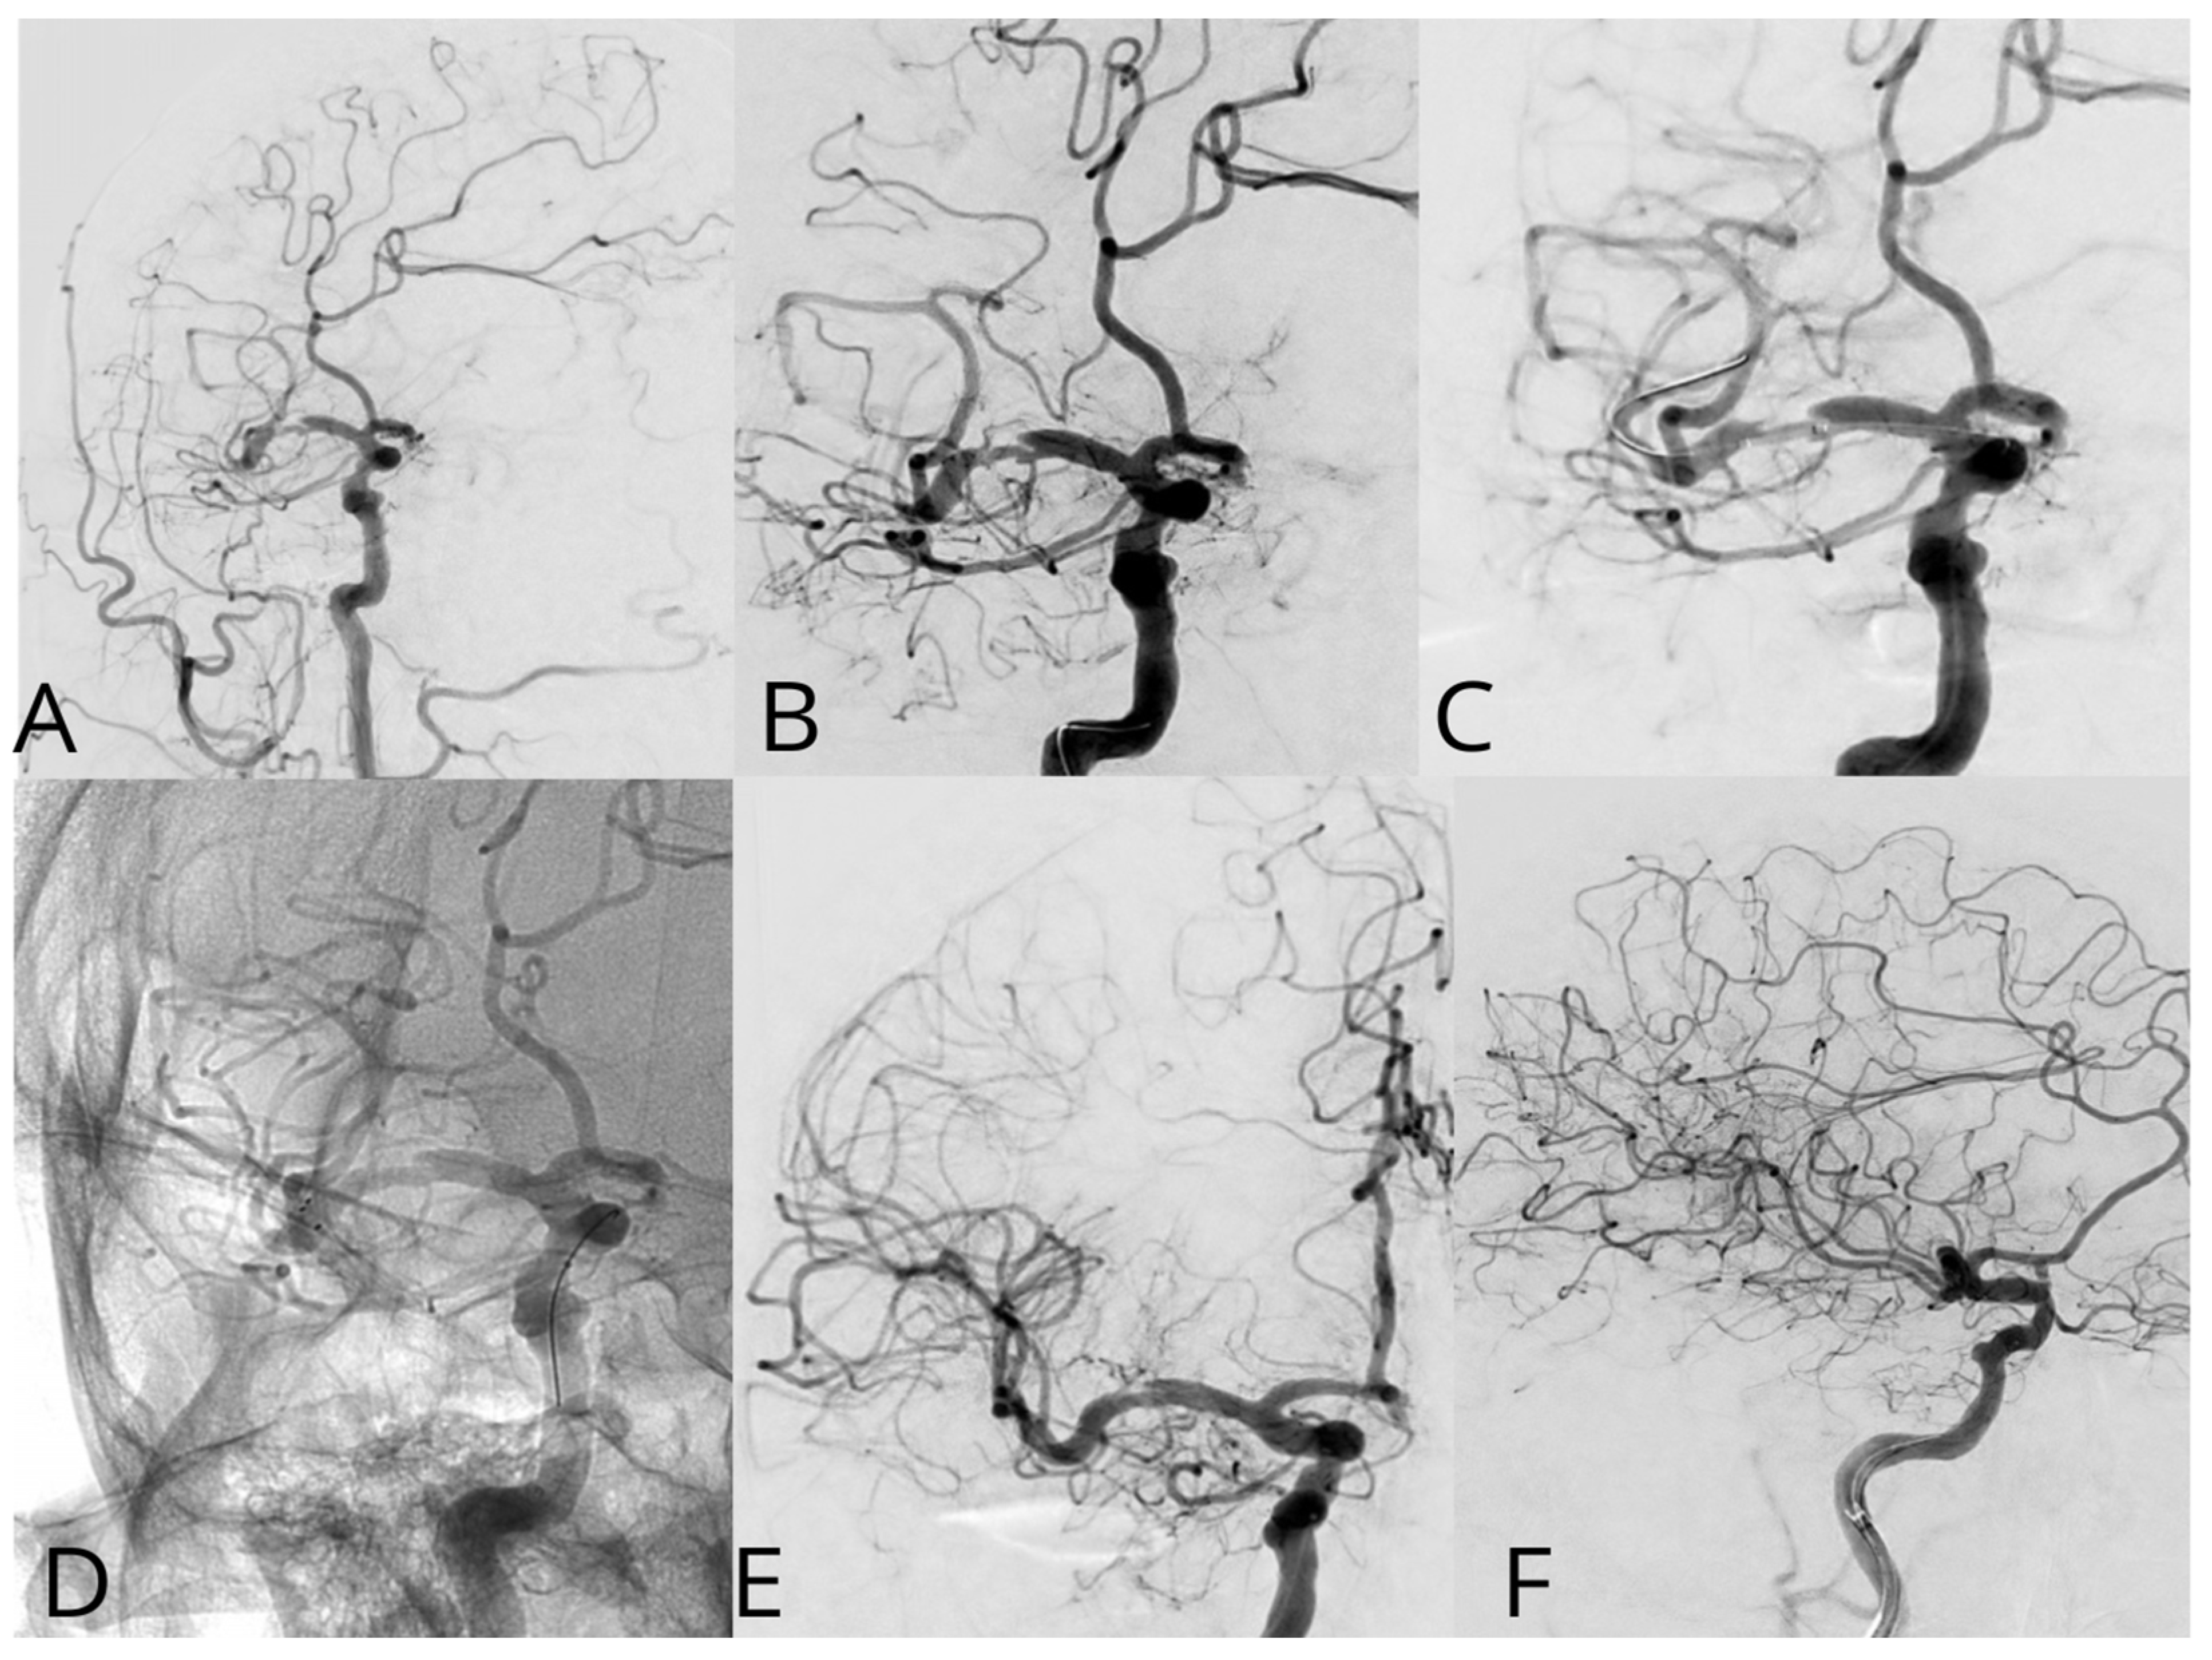

Case #1. A 75-year-old male patient with a history of myocardial infarction, type 2 diabetes mellitus, and hypertension presented with symptoms including slurred speech, temporary followed by full recovery, dizziness, tinnitus, unsteady gait, and lower extremity weakness. According to his wife, these symptoms began one week prior. Further diagnostic imaging with CTA revealed a subocclusion of the basilar artery, moderate stenosis in the V1 segment of the right vertebral artery, and hypoplasia of the left vertebral artery. Neurological examination at the time of admission was unremarkable. The patient was placed on dual antiplatelet therapy, and the VerifyNow test was performed, which detected no resistance. A surgical procedure was performed under local anesthesia. A 7Fr Fubuki guide catheter was inserted into the right vertebral artery, as seen in Figure 4. Under surgical guidance, an ASAHI Sion blue 0.014 × 180 cm microwire was advanced through the stenotic area. A NeuroSpeed 2 × 8 mm catheter balloon was then advanced along the microcatheter, and inflated twice for 2 s within the stenotic segment, resulting in a residual stenosis of up to 40%. Subsequently, a 5.0 × 25 mm Credo intravascular stent was deployed through the NeuroSpeed catheter balloon. Angiographic control confirmed the elimination of the stenosis, and the arteries and veins were found to be patent. At the 3-month follow-up, the patient reported no complaints, and MRI did not show any new signs of stroke.

Figure 4. A diagnostic cerebral angiogram demonstrated an occlusion in the middle segment of the basilar artery on anteroposterior (A) and lateral (B) projections. Balloon angioplasty was performed, as shown in image (C), followed by deployment of a Credo stent, as seen in image (D). Subsequent control angiographies confirmed adequate stent placement and restoration of normal arterial flow on lateral (E) and anteroposterior (F) projections.